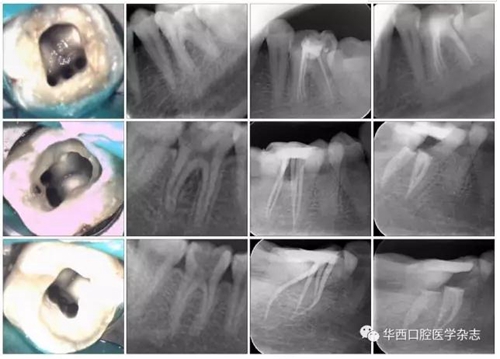

2.2 近中三根管的分型

下頜第一恒磨牙MMC的三種可能解剖形態(tài)見圖4。

從上至下依次為“獨(dú)立”、“歧狀”和“融合”解剖型。

第一列:MMC 顯微鏡 ×16;

第二列:術(shù)前片;

第三列:試尖片;第四列:根充片。

圖4下頜第一恒磨牙MMC的三種可能解剖形態(tài)(Pomeranz分類)

在確定的17顆牙的近中三根管中,顯示“獨(dú)立”解剖(獨(dú)立根尖孔)的2顆(11.8%);顯示“歧狀”解剖(沒有單獨(dú)的根管口)6顆(35.3%);顯示“融合”解剖(具有單獨(dú)的根管口,最終在根尖方向融入到其中一個(gè)主根管)9顆(52.9%)(圖4)。在顯示“融合”解剖的9顆牙的近中三根管中,6顆融合到近中舌側(cè)根管,3顆融合到近中頰側(cè)根管。